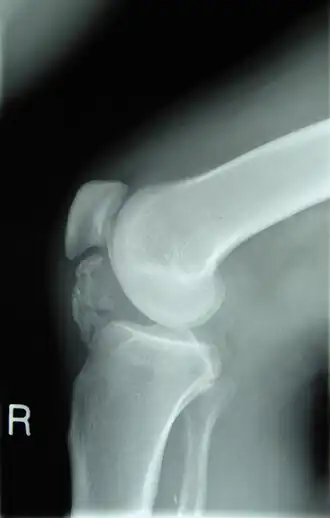

Já a artrite, a inflamação das articulações, pode ser causada por trauma ou infecção. A osteoartrite é uma das formas mais comuns, resultando na destruição da cartilagem articular e na formação de osteófitos ao redor das articulações, muitas vezes associada ao envelhecimento.

No caso do trauma ósseo, as fraturas são uma das principais formas de patologia, ocorrendo quando o osso é submetido a forças anormais de tensão, compressão ou torção. As fraturas podem ser classificadas como completas, incompletas (fratura em galho verde), cominutivas ou compostas. Algumas fraturas, como as resultantes de traumas patológicos, ocorrem devido ao enfraquecimento prévio do osso por doenças como a osteoporose.